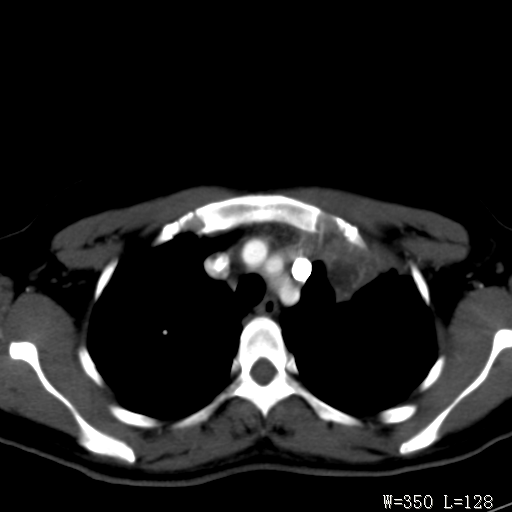

标题: CT27017:1、肺结核?2、永存左上腔静脉。 [打印本页]

标题: CT27017:1、肺结核?2、永存左上腔静脉。

女,32岁,自述肺结核治疗多年复查。

1)考虑左肺上叶肺脓肿,节段性肺不张。2)永存左上腔静脉。

1)考虑左肺上叶节段性肺不张。原因?2)永存左上腔静脉。

支持肺脓肿;还是双上腔静脉确切些吧,回流至冠状窦或右心房。

考虑左肺上叶胸腺瘤可能性大。肺不张/永存左上腔静脉

胸骨后偏左侧囊实性病灶,考虑胸腺瘤可能性大.

1、胸骨后偏左侧囊实性病灶,考虑胸腺瘤可能性大。2、永存左上腔静脉。